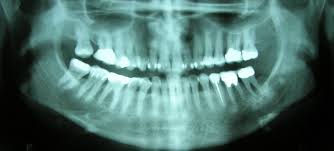

An Introduction To Oral Cancer Dental Supplies And Equipment Dentaltix from www.dentaltix.com Gum cancer is an oral cancer. While symptoms could mean lip cancer, they very well could be due to something far less concerning. Most symptoms of throat cancer aren't specific to cancer, so you'll need to be extra vigilant about watching your oral cavity. Mouth cancer (also known as oral cancer) can occur anywhere inside your mouth — in your lips, gums, tongue, under your tongue, on the roof of your mouth, inside your cheeks and around your wisdom teeth. The areas to which cells have spread vary according to the type of oral cancer. Stop using tobacco or don't start. According to the merck manual, jaw cancer can occur either on the upper jaw, known as the maxilla, or the lower jaw, known as the mandible. Cancer that starts in the middle part of the throat is called oropharyngeal cancer.

Early on these symptoms are quite mild. Some of the most common oral cancer symptoms and signs include: These cancers start when cells in the oral cavity or oropharynx grow out of control and crowd out normal cells. According to the merck manual, jaw cancer can occur either on the upper jaw, known as the maxilla, or the lower jaw, known as the mandible. In the same general area as before, like nearby lymph nodes. Mouth cancer (also known as oral cancer) can occur anywhere inside your mouth — in your lips, gums, tongue, under your tongue, on the roof of your mouth, inside your cheeks and around your wisdom teeth. 44 years experience family medicine. Certain strains of hpv can also put you at risk. The skin may feel thicker or. A thorough oral cancer screening should take about three minutes. Stop using tobacco or don't start. That was another 6 or 8 months. Treatment for lip cancer is similar to that for other types of oral cancer.

The skin may feel thicker or. Oral cancer often starts as a tiny, unnoticed white or red spot or sore anywhere in the mouth. Cancer that starts in the mouth is called oral cavity cancer. This screening is noninvasive and doesn't involve radiation. While symptoms could mean lip cancer, they very well could be due to something far less concerning. Signs of penile cancer include sores, lumps, discharge, and bleeding. For oral cavity cancers, the tumor is growing into nearby structures, such as the bones of the jaw or face, deep muscle of the tongue, skin of the face, or maxillary sinus. However, you can reduce your risk of mouth cancer if you: A thorough oral cancer screening should take about three minutes. Gum cancer is an oral cancer. Mouth cancer (also known as oral cancer) can occur anywhere inside your mouth — in your lips, gums, tongue, under your tongue, on the roof of your mouth, inside your cheeks and around your wisdom teeth. Now that you know a few ways you can tell if you have cancer of the mouth, you must learn about the causes. If you are not getting one, you should find a new dental practice.